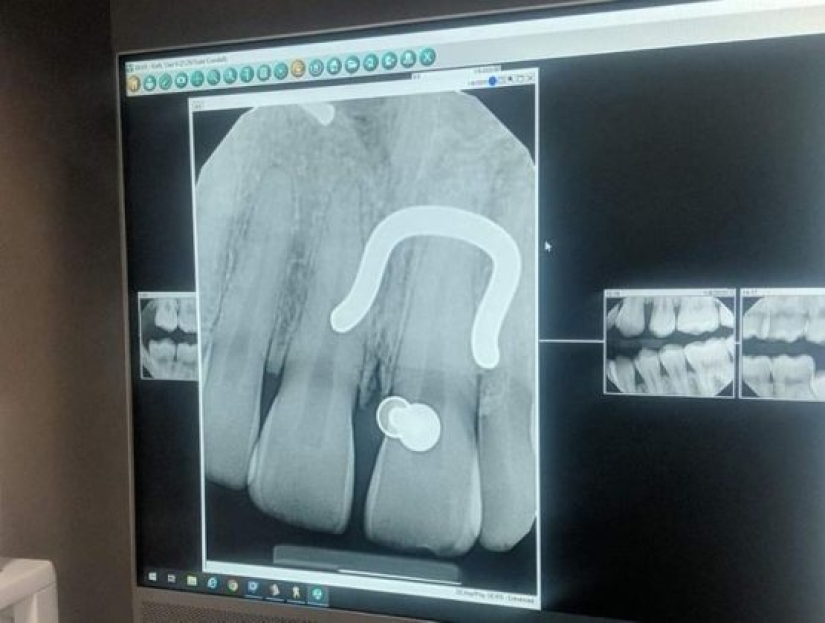

7. "Me tomaron una radiografía de la perforación".